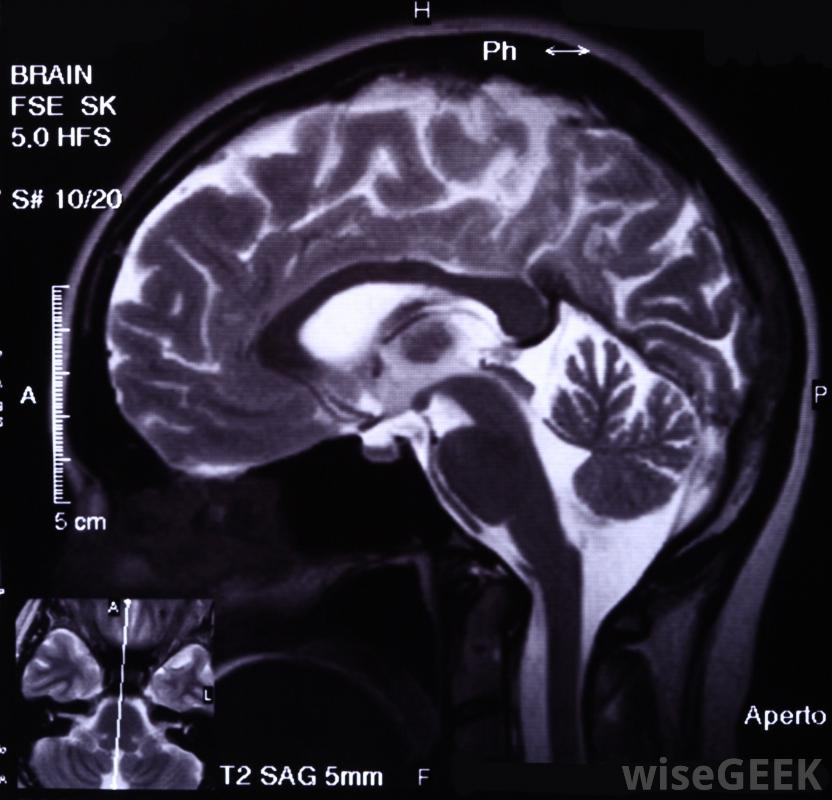

光遺傳學是利用遺傳和光學技術相結合的方法來控制細胞的活動。這種方法始于發現在光照下產生細胞反應的生化物質。通過分離編碼這些蛋白質的基因,科學家用它們來刺激其他活細胞的光反應。從光遺傳學獲得的知識使研究人員對各種疾病過程有了更深入的了解。科學家能夠利用光遺傳學刺激活細胞對光的反應。在20世紀70年代,科學家們發現,某些生物體產生的蛋白質控制著通常通過細胞膜的電荷。當暴露在特定波長的光下時,這些蛋白質會引起細胞間的相互作用。這些蛋白質通常被稱為G蛋白,在這段時間里,研究人員發現細菌視紫紅質對綠光有反應。進一步的研究發現了視紫質家族的其他成員,包括溝道視紫紅質和鹽紫質醫生使用醫學成像和光遺傳學來繪制大腦內的路徑在2000年至2010年的十年間,神經科學家發現有可能提取出視蛋白基因并將其插入其他活細胞中,然后這些細胞獲得同樣的光敏性。最初使用的方法之一是去除視蛋白基因,將它們與良性病毒結合,把它們插入培養皿中的活神經元。當注入的細胞暴露在綠光脈沖下時,神經元的反應是打開離子通道。當通道打開時,細胞接收到離子的涌入,從而產生電流,開始與另一個神經元的通訊。科學家發現其他G蛋白對不同的光顏色有反應,抑制或增強鈣離子通道和腎上腺素的釋放。研究最終從將光遺傳學應用于一小群活細胞到使用活體哺乳動物實驗。通過將視蛋白基因導入小鼠大腦,細胞開始產生G蛋白。利用這些G蛋白和光纖,科學家們能夠控制神經元的放電速度。他們還開發了一種方法,將一根小光纖轉換成電極,以提供細胞活動的電讀數。這種腦-計算機接口允許研究人員評估和通過結合磁共振成像(MRI)和光遺傳學,研究人員能夠繪制出大腦內的神經活動和路徑,通過探索神經功能的復雜性,醫生們可以更好地理解什么是正常和異常的大腦活動與藥物和電療不同,光遺傳學允許調節特定的細胞和通路,從光遺傳學獲得的知識和技術也允許控制心臟細胞、淋巴細胞和分泌胰島素的胰腺細胞的功能。